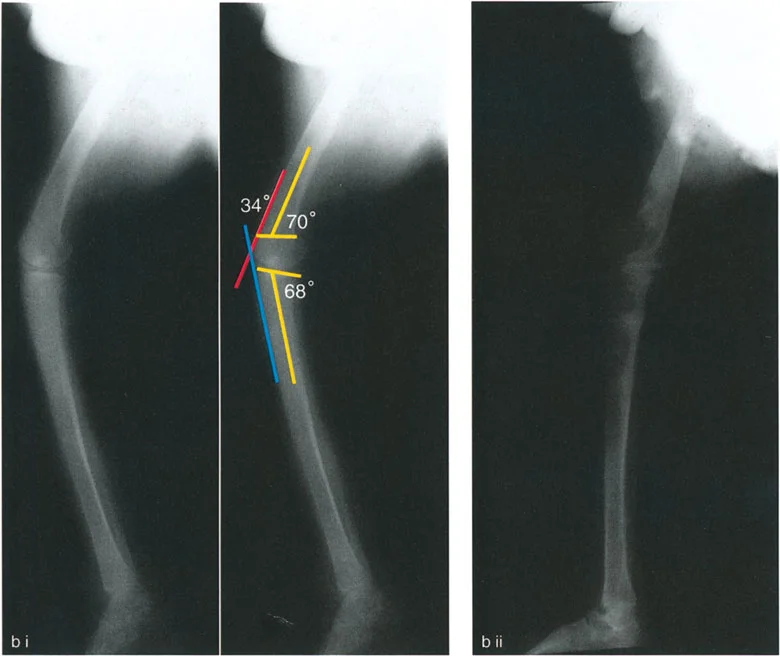

تُعد الأشعة التصويرية ضرورية لتأكيد التشخيص وتحديد مدى الضرر وموقع التشوهات العظمية بدقة:

- الأشعة السينية (X-rays):

- الأشعة الأمامية الخلفية (AP View) والجانبية (Lateral View): تُظهر حالة العظام، تآكل الغضروف (يُلاحظ كضيق في المسافة المفصلية)، وجود نتوءات عظمية (Osteophytes)، وأي تشوهات عظمية واضحة.

- الأشعة السينية الطويلة للطرف السفلي بالكامل أثناء الوقوف (Standing Long-Leg AP View): تُعد هذه الأشعة حاسمة لتقييم المحاذاة الميكانيكية للطرف السفلي بأكمله. تُظهر بدقة درجة الانحراف الأفحج (Varus) أو الأروح (Valgus) وتساعد في تحديد مركز دوران التشوه (CORA).

- الأشعة الجانبية الطويلة للطرف السفلي بالكامل أثناء الوقوف في أقصى بسط (Standing Long-Leg Lateral View in Maximum Extension): تُستخدم لتقييم تحدد حركة الركبة (FFD) والركبة الارتدادية (Recurvatum)، وتحديد ما إذا كان التشوه عظميًا أو ناتجًا عن تقلص في الأنسجة الرخوة.

تصحيح تحدد حركة الركبة (Flexion Deformity - FFD)

تحدُّد حركة الركبة هو عدم القدرة على مد الركبة بالكامل. يمكن أن يكون سببه عظميًا أو ناتجًا عن تقلص في الأنسجة الرخوة.

- التشخيص الدقيق: يجب تحديد ما إذا كان تحدد الحركة ناتجًا عن تشوه عظمي (تقوس أمامي في الفخذ أو الساق) أو تقلص في الأنسجة الرخوة (الأوتار الخلفية، محفظة المفصل).

- قطع العظم التمديدي (Extension Osteotomy):

- إذا كان التشوه عظميًا، يتم إجراء قطع عظم تمديدي في عظم الفخذ أو الساق لتصحيح التقوس.